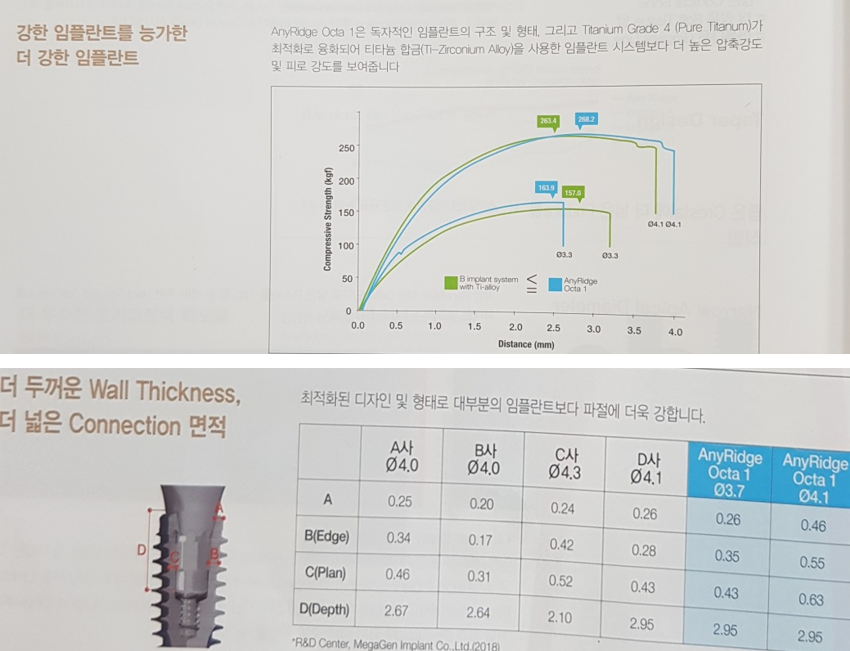

1) Fixture or/& Abutment fracture, Screw loosening

• Small diameter fixture(3.5mm 직경 )에서 많이 발생

- High

occlusal load area(대구치, 특히 싱글인 경우)에서는 위험;

구치부 단일 임프란트는 최소한 지름이 4.5mm 4.8mm, 5.0mm 이상의 것을 사용

• fixture 내부 속으로 체결되는 abutment 때문에 생기는 구조적 한계로 어벗먼트와

픽스쳐의 파절 가능성이 비교적 높다는 최대 단점을 갖고 있다.

이렇게 찢어지는 것을 보완하기 위해서 나온 임플란트가 소위 스트라우만의 ITI implant다. Bone level에서 gingiva level로 올라오면서 픽스쳐 두께가 강화된 것이다.

구조적

한계

구조적 취약성을 극복하기 위해서 재료의 업그레이드가 계속 되고 있다. 재료적 측면 뿐만 아니라 기계적 측면에서도

이득을 얻어야 한다. Convertible ab 가 해결책이 될 수 있다.